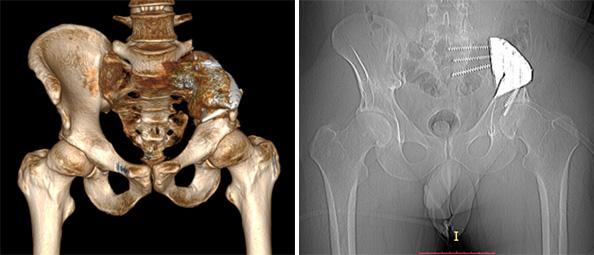

Рафаэль прошел несколько циклов полихимиотерапии, что позволило добиться стабилизации состояния. Одновременно с проведением химиотерапевтического лечения началось проектирование индивидуального эндопротеза с использованием 3D-принтинговых технологий. Из-за нестандартной резекции на этапе предоперационного планирования сначала был создан макет таза и эндопротеза. Затем методом послойного лазерного плавления титанового порошка на 3D-принтере в петербургской компании «Остконнект» был изготовлен имплант.

В конце марта 2020 года была выполнена сложнейшая операция по резекции левой подвздошной кости и крестца с одномоментным протезированием индивидуальным 3D-принтинговым эндопротезом.

Вмешательство выполнил Георгий Иванович Гафтон, д.м.н., руководитель научного отделения общей онкологии и урологии НМИЦ онкологии им. Н.Н. Петрова. Операция длилась 5 часов, пациенту удалось сохранить тазобедренный сустав и сосудисто-нервные структуры.